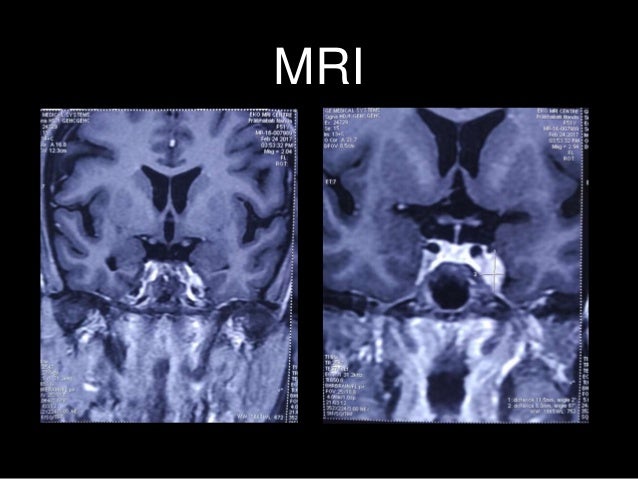

Onset can occur at any age. 1 Signs and symptoms include a constant pain behind the eye. MRI and clinical features are suggestive of Tolosa-Hunt syndrome.